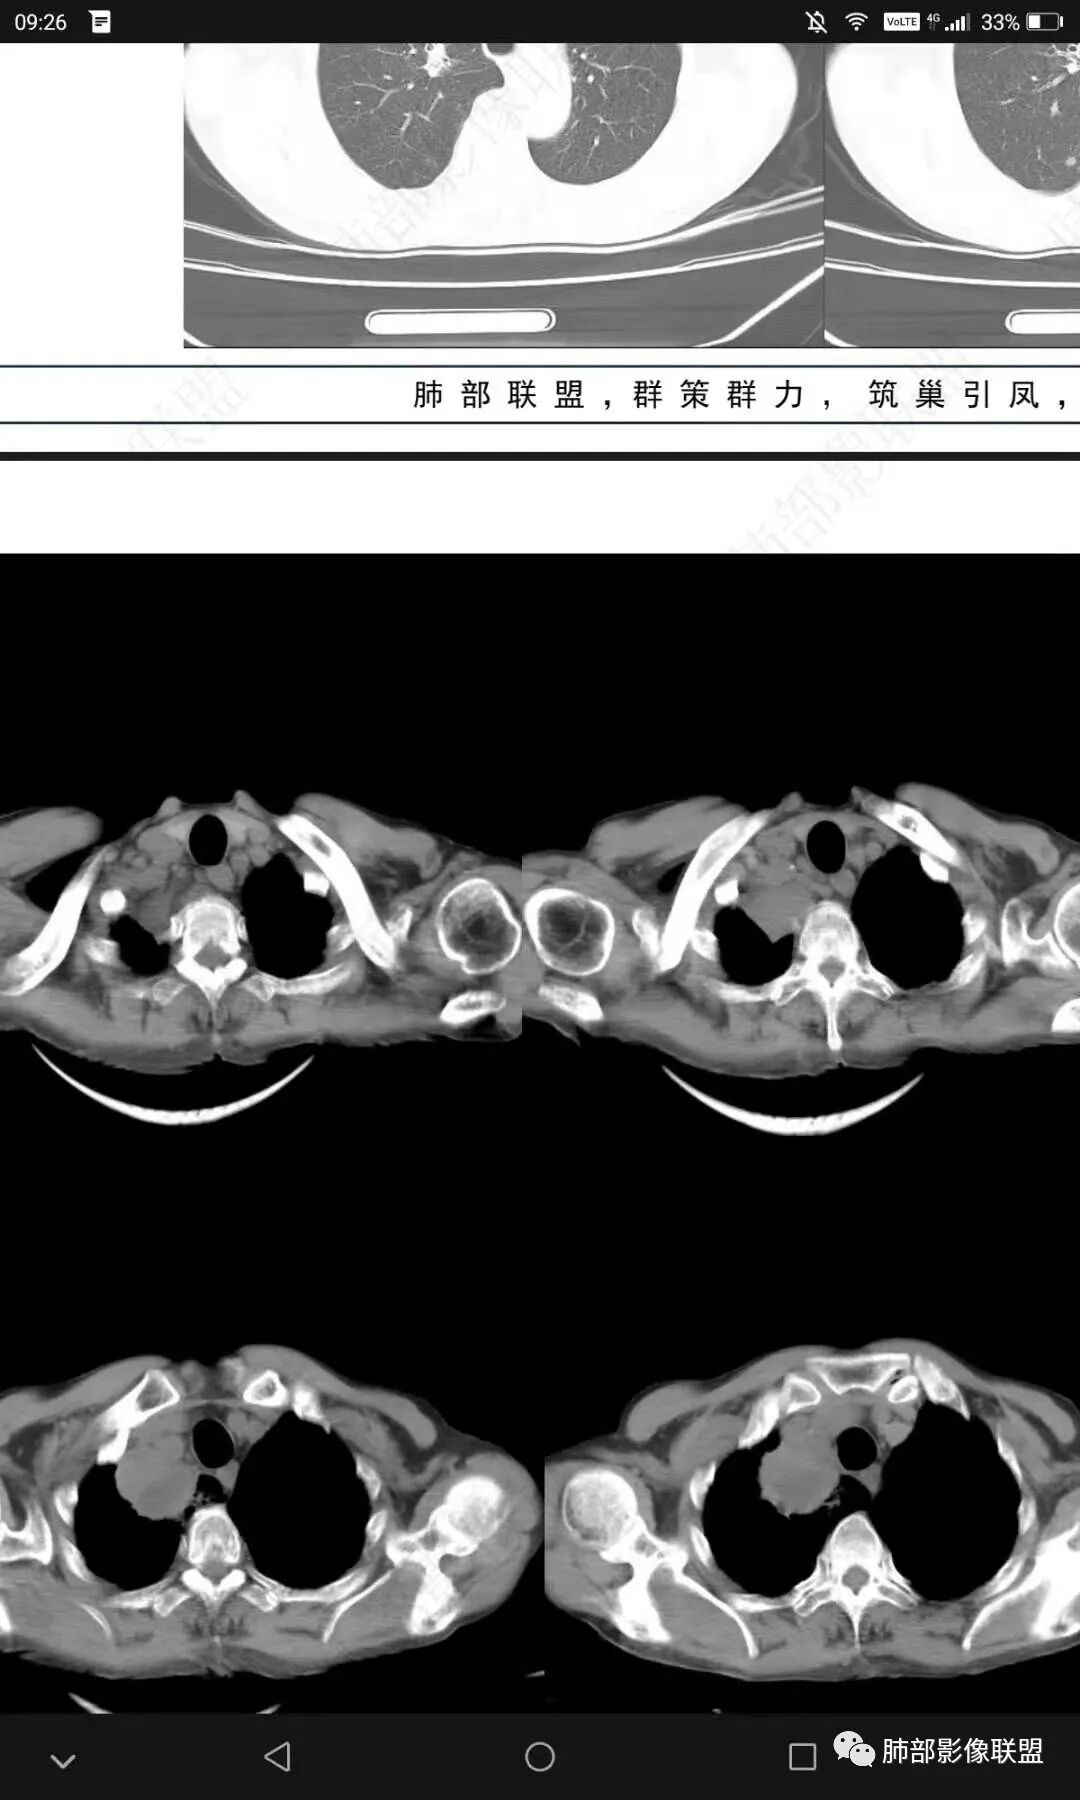

老年人,有高血压、脑梗死、肾结石病史

这次,半月,左胸痛不适,高热:39°C,白细胞、中性粒细胞高

右下叶背段有结节

主病灶在右上叶尖段、前段纵隔旁,紧贴胸膜

楔形、边缘膨隆,附近见斑片状、网格状高密度影

支气管近端堵塞,可惜显示的不一定全面

中央坏死明确

1月后,发热再次入院

这些新发的

合并有胸水

出现液气平面

治疗一周后复查

周围干净了,液平小了

壁似乎均匀了